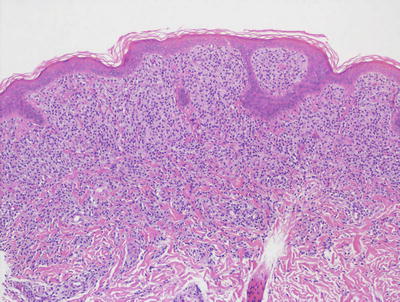

In LCH, the epidermis demonstrates focal parakeratosis overlying varying degrees of spongiosis that is diffuse throughout the epidermis. In most cases, there is abundant exocytosis of Langerhans cells into the epidermis (Fig. 22.3). Langerhans cells can usually be identified based upon cytologic features that include reniform-shaped, grooved, or folded nuclei and abundant cytoplasm (Figs. 22.4 and 22.5). Anti-CD1 a immunohistochemistry is useful in cases when the nature of the infiltrating cells is not readily apparent. Intraepidermal eosinophils are also quite common. Cytologic atypia and significant mitotic activity are rarely encountered. Some cases fail to demonstrate exocytosis of Langerhans cells into the dermis. Treatment with topical corticosteroids prior to biopsy may also suppress exocytosis and mask the diagnostic features.

Fig. 22.3

Marked epidermotropism of Langerhans cells into the epidermis is seen in most cases of Langerhans cell histiocytosis